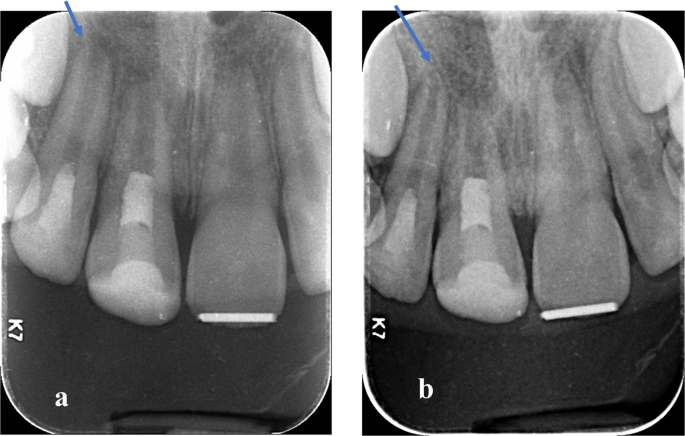

Continued root lengthening was observed in this study, the mean increase in root length in mm and percentage between 12 months follow-up and pre-operative root length in Group (N) was 1.03 (±ā0.97)āmm, 8.52(±ā3.33)% and in Group (W) was 1.04 (±ā0.86)āmm, 8.64(±ā4.30)% with no significant difference between both groups. Mean and Standard deviation (SD) values are shown in TableĀ 4. Digital radiographs showing an increase in root length in Group (N) and (W), Figs.Ā 7, 8.

a Baseline immediate post-operative radiograph showing the immature root of upper right lateral incisor. b 12 months follow-up radiograph showing the increase in root length in upper right lateral incisor.